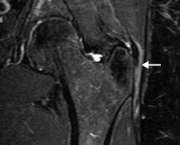

A bursite Trocanteriana é uma inflamação em uma ou mais bursas encontradas na articulação do quadril. Esta bursite pode ser causada por uma queda ou golpes ao lado do quadril, atrito associado a uso excessivo, pé pronado ou fraqueza de glúteo médio.

Um destes fatores presentes gerará a inflamação e consequente dor durante uma corrida, desajuste no andar da pessoa ou crepitação na articulação. O tratamento deve ser realizado conforme a causa da doença, por exemplo, se for por fraqueza de glúteo, deve-se fortalecer glúteo.